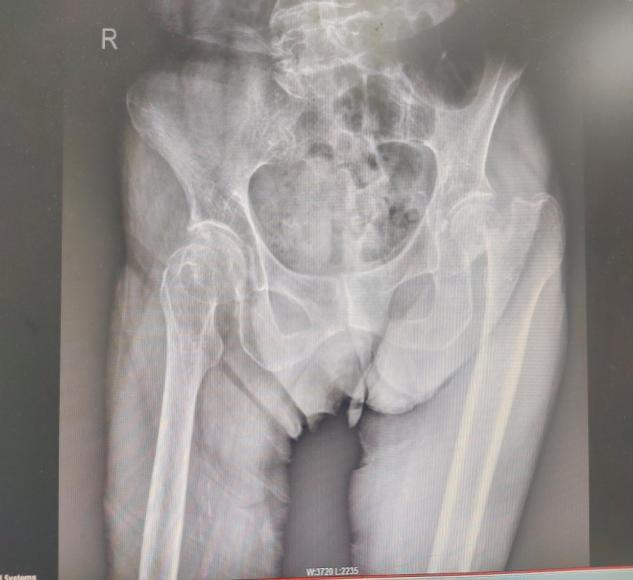

近日,近100歲高壽的潘奶奶,在家上廁所時(shí)不慎摔倒,導緻左股骨頸骨折(頭下型),其家屬急忙將(jiāng)潘奶奶送至惠州六院急診科。經(jīng)急診醫生初步評估後(hòu)轉送至惠州六院關節外科、運動醫學(xué)科病區,經(jīng)過(guò)術前檢查發(fā)現,潘奶奶左股骨頸骨折,又有重度骨質疏松症、雙側髋關節退行性變等20項病症。患者高齡,基礎疾病多,手術風險高。

8月15日,由關節外科、運動醫學(xué)科主任餘金勝主刀,帶領手術團隊成(chéng)功進(jìn)行左側人工股骨頭置換術,術中用時(shí)不到30分鍾成(chéng)功置入髋關節假體,整個手術用時(shí)約80分鍾,術中仔細止血,術中無需輸血。